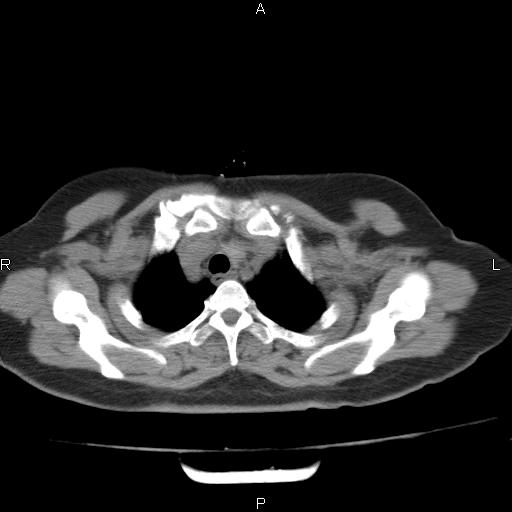

胸腺瘤

女、63Y 双眼睑下垂,早轻晚重。 胸腺瘤???

结果胸腺瘤